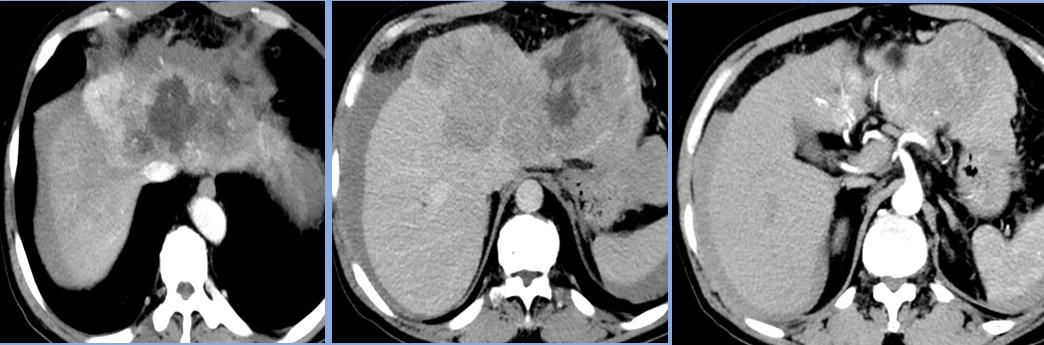

肝中、肝左静脉,门静脉左支受侵;诊断性腹腔穿刺,抽出不凝固血液 Child-pugh*级A**5分,AFP 914.10 ng/ml

后来家属打听到有一种微创介入的方法,副作用相对较轻,可以治疗肝癌。为了寻求进一步的治疗,患者找到了唐田主任。入院后经会诊后,决定对肖先生采用介入综合治疗,也就是在影像设备的引导下,经左侧手臂肱动脉入路,将特制的导管、导丝等精密器械对体内肿瘤进行针对性的诊治。

肝左动脉供血 碘化油:20ml+THP:50mg栓塞微球(300um) 肝右叶子灶形成

3个月后复查CT显示碘化油沉积效果好 AFP: 16.9ng/ml